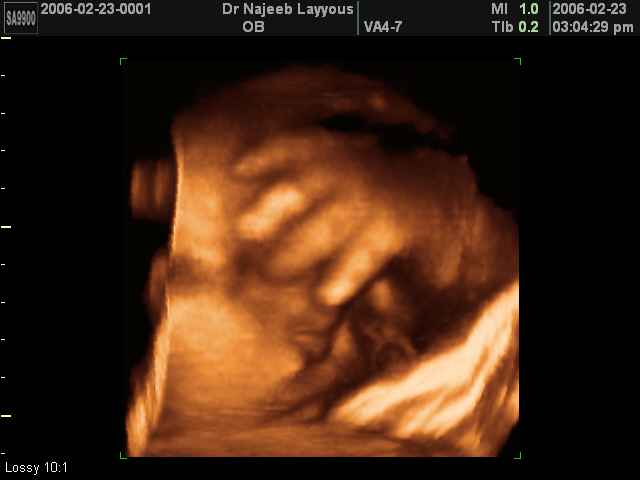

- 3D Fetal Limbs Ultrasound Scan Photos

3D Ultrasound Scan Photos of Fetal Limbs | Dr N Layyous